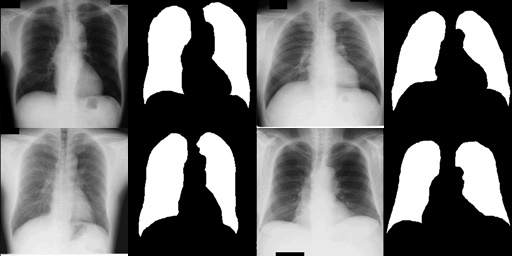

Figure 1: Sample of the JSRT dataset [8] with X-ray images and

corresponding lung masks

It was deemed suitable for our work since the dataset was widely accepted and benchmarked, and had been refined through years of preprocessing by various researchers. Since the dataset consisted of a relatively small number of data points, it was also suitable for low-resource intensive applications leading to greater accessibility. The Figure 1 provides a small sample of the dataset for reference as to what the input would ideally look like.